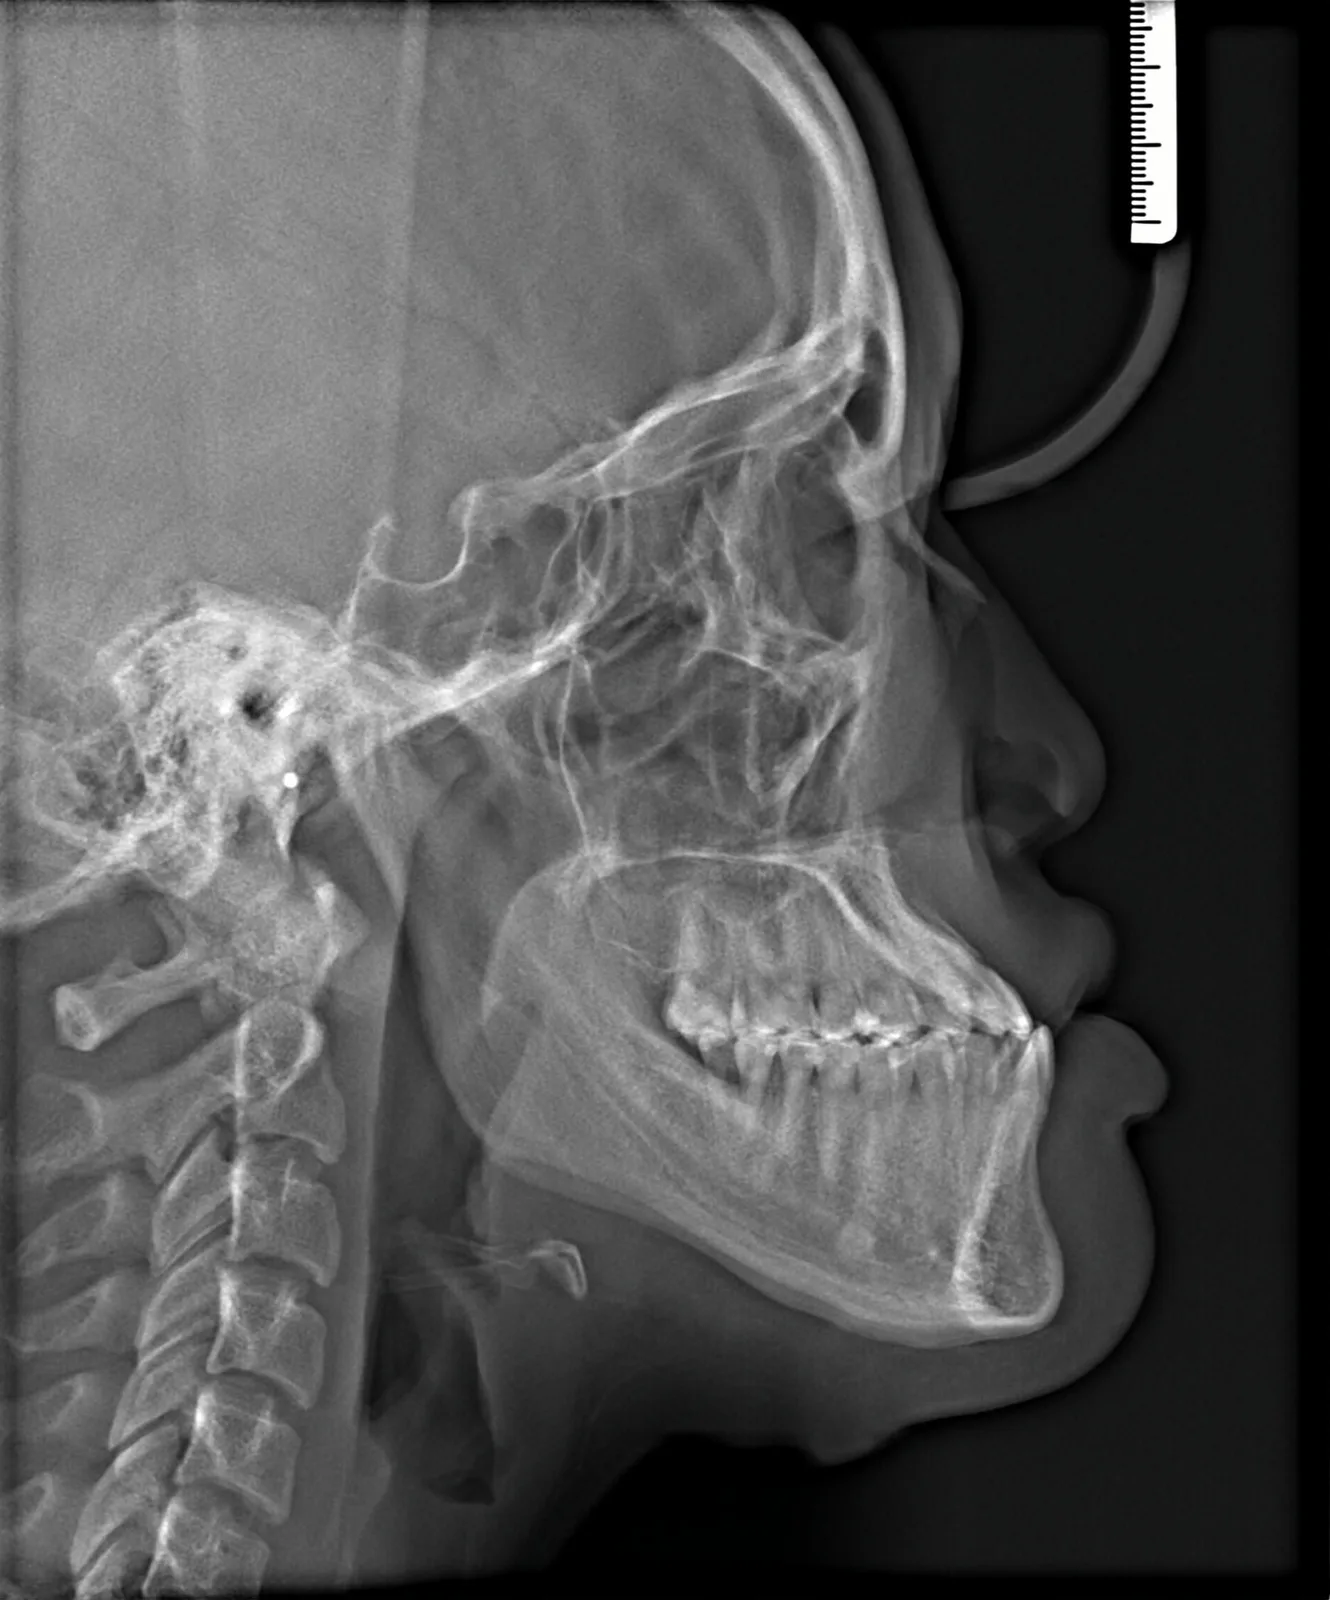

Before Metal Self-Ligating Braces & Orthognathic Surgery: The Surgical Comeback case study at AOB Orthodontics in Las Vegas. Clinical diagnosis: showing a severe skeletal imbalance that braces alone could not correct. Before

Before orthodontic x-ray: Cephalometric profile before Metal Self-Ligating Braces & Orthognathic Surgery showing skeletal relationship. Before

This case began with a severe skeletal imbalance that braces alone could not correct. The patient presented with a significant Class III bite, asymmetric mandibular prognathism, anterior crossbite, and midline deviation. Because the jaw relationship was the root of the problem, a combined orthodontic and surgical approach was required to achieve the best stable, long-term result.